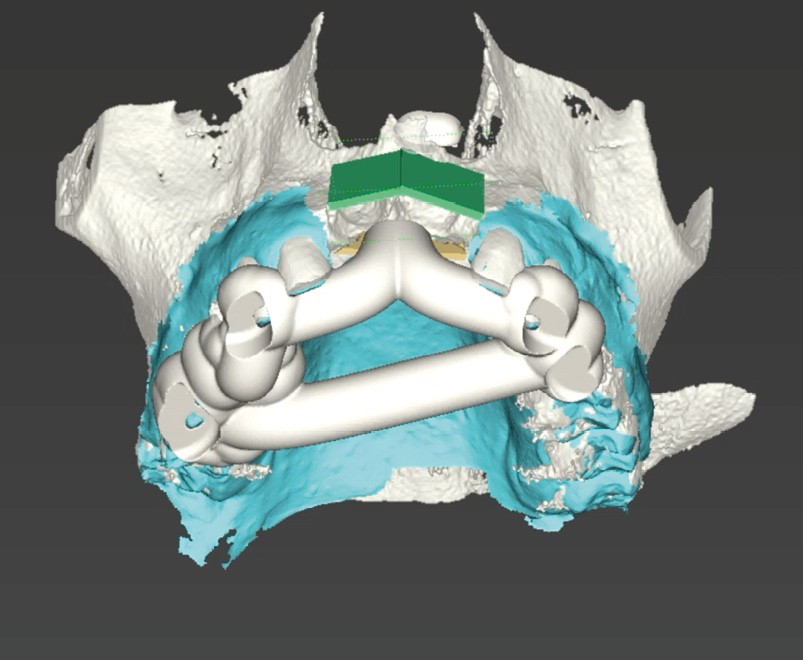

La chirurgie guidée dynamique permet, quant à elle, de prélever par piezochirurgie (Piezotouch, Mectron) de façon naviguée (fig. 3). Ainsi, le bloc peut être designé en amont sur le logiciel de planification implantaire pour correspondre parfaitement au défaut osseux en présence, et prélevé à l’identique sur la ligne oblique externe (fig. 4 à 8).